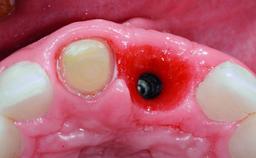

Replacement of an Upper Right Central Incisor with Root Resorption: Ridge Preservation, Delayed Placement of an NC Bone Level Roxolid Implant

# of Implants | 1 |

Type of Implants | Reduced-Diameter|Two-Piece |